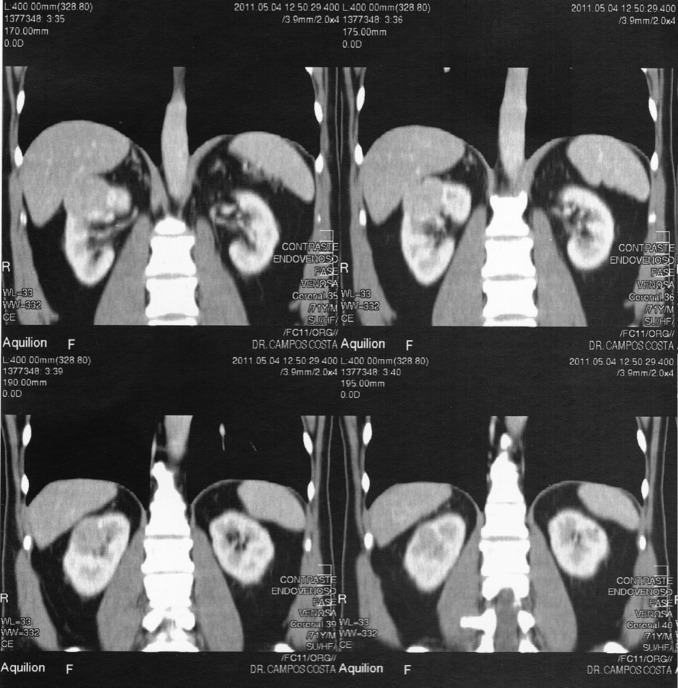

Na consulta de seguimento encontrava‐se assintomático e o exame físico era normal. O estudo analítico trazido pelo doente apresentava as seguintes alterações: glicose 134 mg/dL, HbA1c 6,9%, colesterol total 204 mg/dL, colesterol HDL 34 mg/dL, colesterol LDL 123,6 mg/dL, triglicerídeos 232 mg/dL e creatinina plasmática 1,4 mg/dL (taxa de filtração glomerular estimada [TFGe] – Modification of Diet in Renal Disease [MDRD] – 53,10 mL/min/1,73 m2 ). O exame sumário da urina era normal. Perante o aumento da creatinina plasmática relativamente ao último estudo analítico realizado 6 meses antes (1,25 mg/dL; TFGe – MDRD – 60,69 mL/min/1,73 m2 ), foi solicitada uma ecografia renal que revelou uma formação nodular sólida, de contornos regulares, parcialmente exofítica, na vertente anterior da metade superior do rim direito, com 4,4 × 4,3 cm de diâmetro, sugestiva de neoformação primitiva. O restante exame era normal. Foi realizado estudo complementar com tomografia axial computorizada com contraste ( Figura 1  ;  Figura 2 ), confirmando‐se uma lesão nodular sólida no polo renal superior direito, captante de contraste, com 4,7 × 3,7 × 3,2 cm de diâmetro, com contacto posterior com o lobo hepático direito, compatível com neoplasia de células renais. Perante este diagnóstico, o doente foi referenciado para uma consulta urgente de urologia, tendo sido submetido a nefrectomia radical laparoscópica em junho de 2011. O exame macroscópico da peça cirúrgica revelou uma neoplasia de 4,0 × 4,0 × 4,2 cm de diâmetro, bem delimitada, não capsulada e de localização cortical. No exame histológico, observou‐se uma neoplasia epitelial bem delimitada, revestida por fina cápsula fibrosa, e constituída por toalhas de células de citoplasma amplo, granular e eosinófilo, com núcleos redondos e regulares, com ligeira atipia. O índice mitótico era baixo e não se observou necrose, permeação venosa, linfática ou perineural, nem invasão da cápsula renal. Estes resultados foram diagnósticos de oncocitoma renal.

Resultados da tomografia axial computorizada abdominal com contraste (cortes ...

Figura 1.

Resultados da tomografia axial computorizada abdominal com contraste (cortes longitudinais) – neoformação no polo renal superior direito.